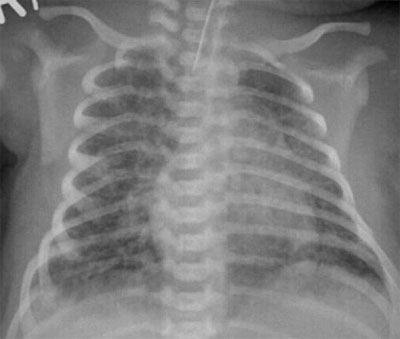

Bilden visar röntgenbild vid mekoniumaspiration.